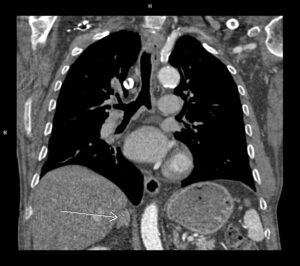

Figura 2: reconstrucție oblic axială MIP (maximum intensity projection) din achiziție angioCT torace și abdomen superior cu evidențierea disecției de arteră mezenterică superioară cu ambele lumene circulante

Discuţie caz nr 128: Valva aortică este bicuspidă prin coaptarea cuspei pentru sinusul Valsalva drept și cuspei pentru sinusul non-coronarian, la nivelul cooptării fiind prezenta o calcificare. Secundar valvei aortice bicuspide se remarca creștere de calibru a aortei ascendente, acesta fiind și motivul îndrumării pacientului la examinare CT de aortă toracică – examinare care ar trebui sa fie efectuată obligatoriu cu sincronizare ECG. Întâmplător, la limita inferioară a câmpului de scanare, la nivelul arterei mezenterice superioare se evidențiază un fald de disecție cu ambele lumene circulante.